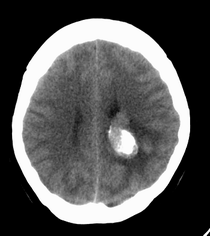

患者,女性,33岁,外伤检查发现,既往没有明显类似病史。

ct平扫见左侧脑室后角不规则形,边界不清的等密度肿块,肿瘤内有钙化,瘤周可见残存的脑室(低密度脑脊液影),考虑脉络脉丛乳头状瘤或室管膜瘤.

左侧侧脑室三角区占位性病变,其特点是平扫边界清、密度高、其内可见大块结节样的钙化,首先考虑起源于侧脑室三角区残余蛛网膜上皮的脑膜瘤可能性最大,无论是形态、密度、好发部位均符合脑膜瘤特点,建议增强进一步检查。

左侧脑室内软组织肿物,内部见多发不规则钙化,边界清楚锐利,有分叶。相应左侧脑室扩张。常见的不外乎3种病:室管膜瘤,脑膜瘤,脉络脉丛乳头状瘤。脑膜瘤分叶较少见,脉络脉丛乳头状瘤钙化较少见,因此,室管膜瘤可能性最大。

1室管膜瘤(肿瘤以膨胀性生长,有包膜,与周围分界清晰,大多位于脑室内ct表现为等密度,稍高密度肿快,边缘不光整呈分爷状。瘤内常见小圆状,块状钙化影。)2脑室内脑膜瘤(多位于侧脑室三角区ct平扫表现稍高于脑组织的肿快,无明显钙化。好发成年女性。)3脉络丛乳头状瘤(易引起交通性脑积水,颅高压症状明显)。总和以上考虑室管膜瘤可能性大。

左侧脑室内见不规则略高密度团块影,边缘分叶,内见多发不规则钙化,病灶与侧脑室壁关系较为密切,左侧脑室扩大。考虑室管膜瘤可能性较大,其次为脑膜瘤,脉络丛乳头状瘤的可能性最小。

患者,女性,33岁,外伤检查发现,既往没有明显类似病史;

1、病灶除钙化外其它部分质均匀,无明显密度差别;

2、病灶界清,呈现膨胀性生长,对周围组织无明显浸润表现;

3、钙化部分范围较大,呈现大片状钙化;

4、病人为成年女性,无明显不适;

考虑:脑膜瘤;

鉴别诊断:室管膜瘤;脉络膜乳头状瘤;

平扫见左侧脑室三角区不规则形肿块,肿瘤内有钙化,瘤周可见残存的脑室(低密度脑脊液影),考虑脉络脉丛乳头状瘤或室管膜瘤.

侧脑室三角区占位,首先考虑脑膜瘤,其次考虑室管膜瘤,室管膜瘤相对密度混杂一些,低一些。脉络丛乳头状瘤可能性不大,因为没有脑脊液明显增多改变,而且成人多在四脑室。

左侧侧脑室内分叶状肿块,其内见块状钙化,见左侧脑室阻塞性积水.考虑:脉络丛乳头状瘤

因病人无交通性脑积水,故脉络丛乳头状瘤不支持,脑室内脑膜瘤及室管膜瘤均有可能,病灶密度较高,前者可能性更大,建议结合增强检查。

左侧脑室后角不规则形,边界尚清的等密度肿块,肿瘤内有钙化。考虑脑膜瘤或室管膜瘤。

ct平扫见左侧脑室后角不规则形,边界不清的等密度肿块,肿瘤内有钙化,瘤周可见残存的脑室(低密度脑脊液影),考虑考虑脑膜瘤